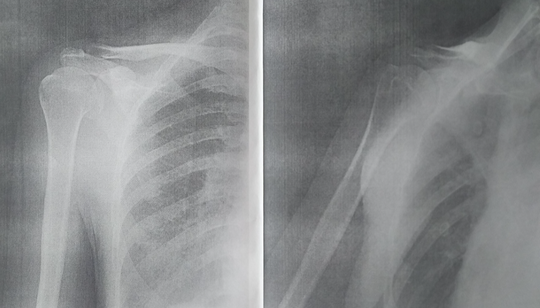

上記患者のX線画像;医師より画像に支障はないと診断。

したがって、構造上の問題よりも機能上の問題が優先される。